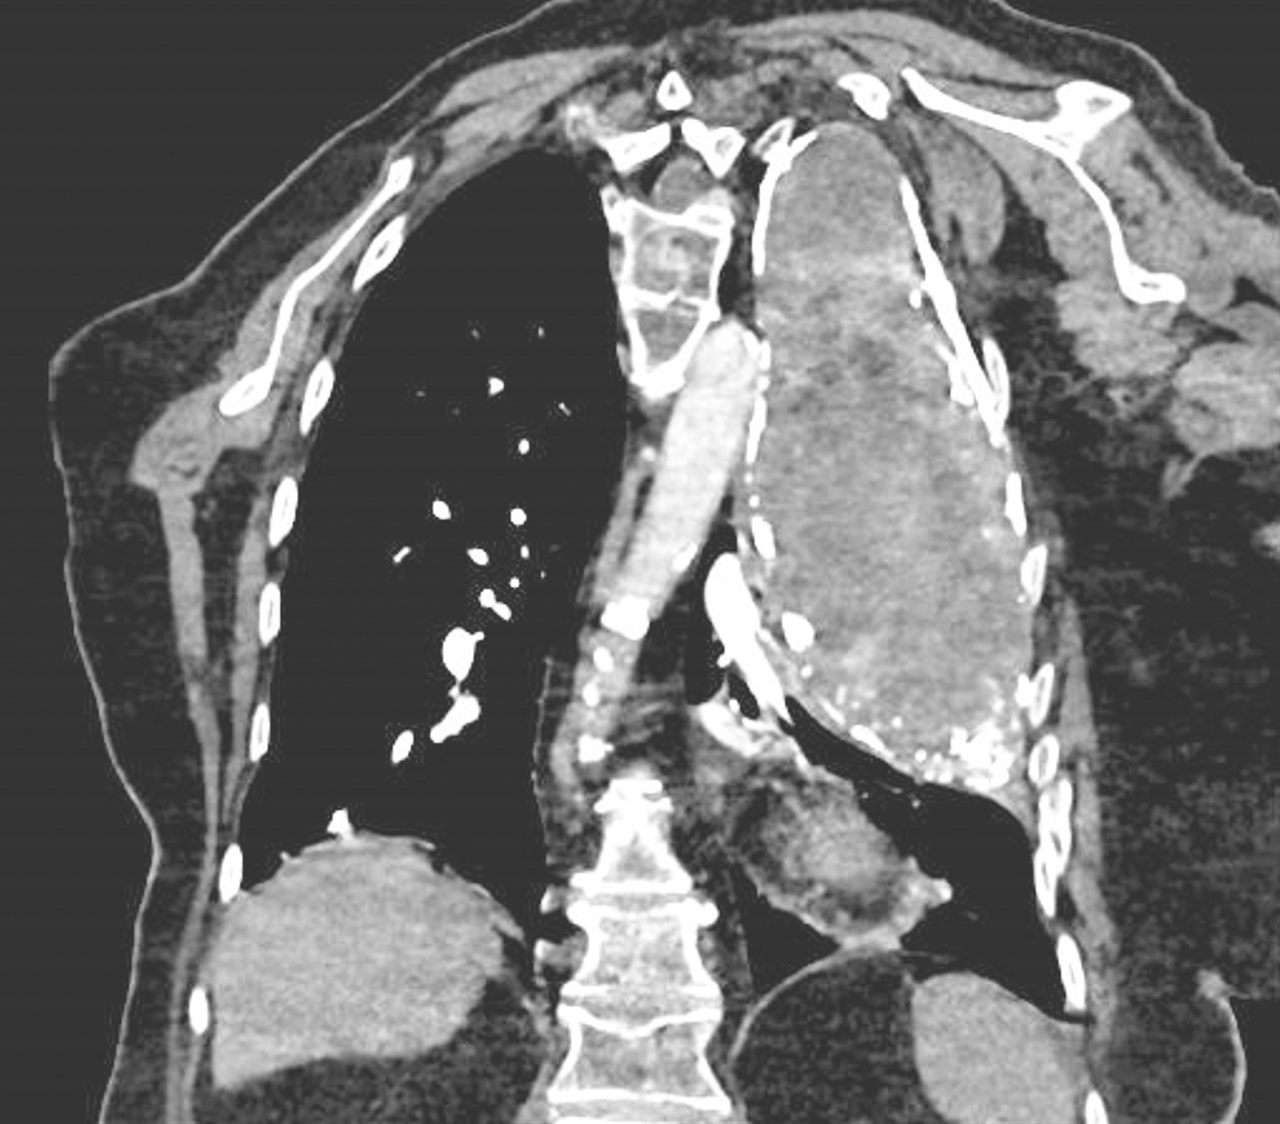

Une femme de 97 ans est hospitalisée pour fièvre et toux. La PCR Covid-19 est positive. Voici son scanner thoracique.

Quel est votre diagnostic ?